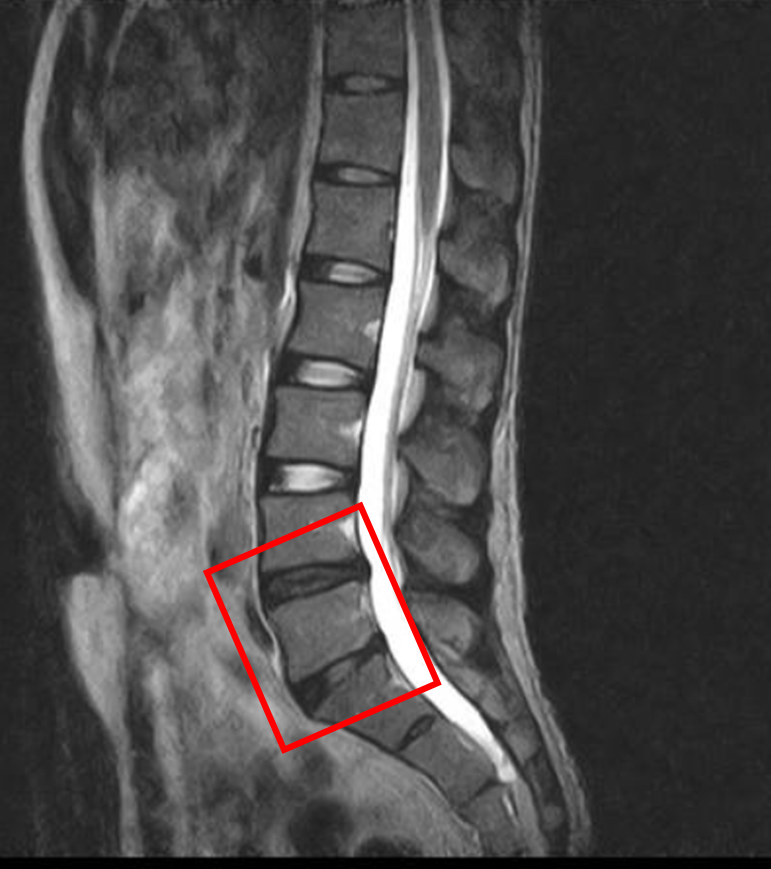

この患者様は赤い枠で示されている箇所(L4/5、5/s)に椎間板変性症を認めます。

画像上では、線維輪断裂などは認めませんでしたが繰り返しの腰痛の原因としては椎間板の可能性が高いです。